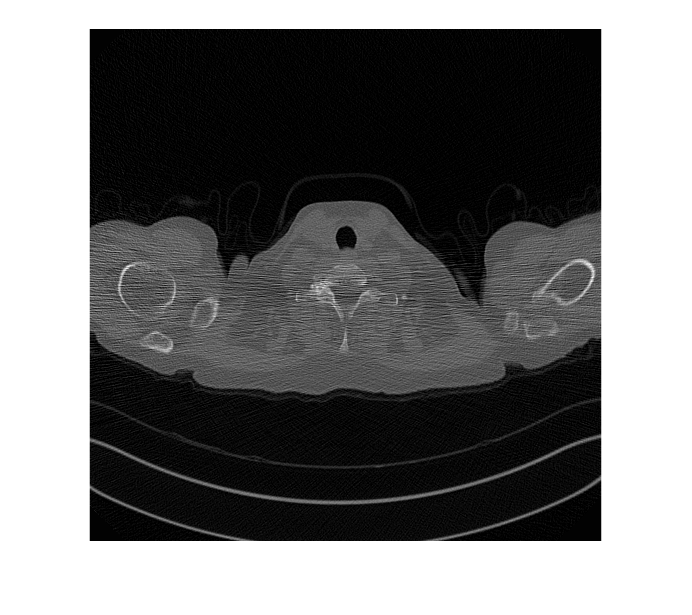

Read and display an image from the datastore of low-dose test images.

idxToTest = 1; imLowDoseTest = readimage(imdsLDTest,idxToTest); figure imshow(imLowDoseTest)

Display the input low-dose CT, the generated high-dose version, and the ground truth high-dose image in a montage. Although the network is trained on data from a single patient scan, the network generalizes well to test images from other patient scans.

imshow([imLowDoseTest,imHighDoseGenerated,imHighDoseGroundTruth]) title("Test Image "+num2str(idxToTest)+ ... ": Low-Dose, Generated High-dose, and Ground Truth High-dose")